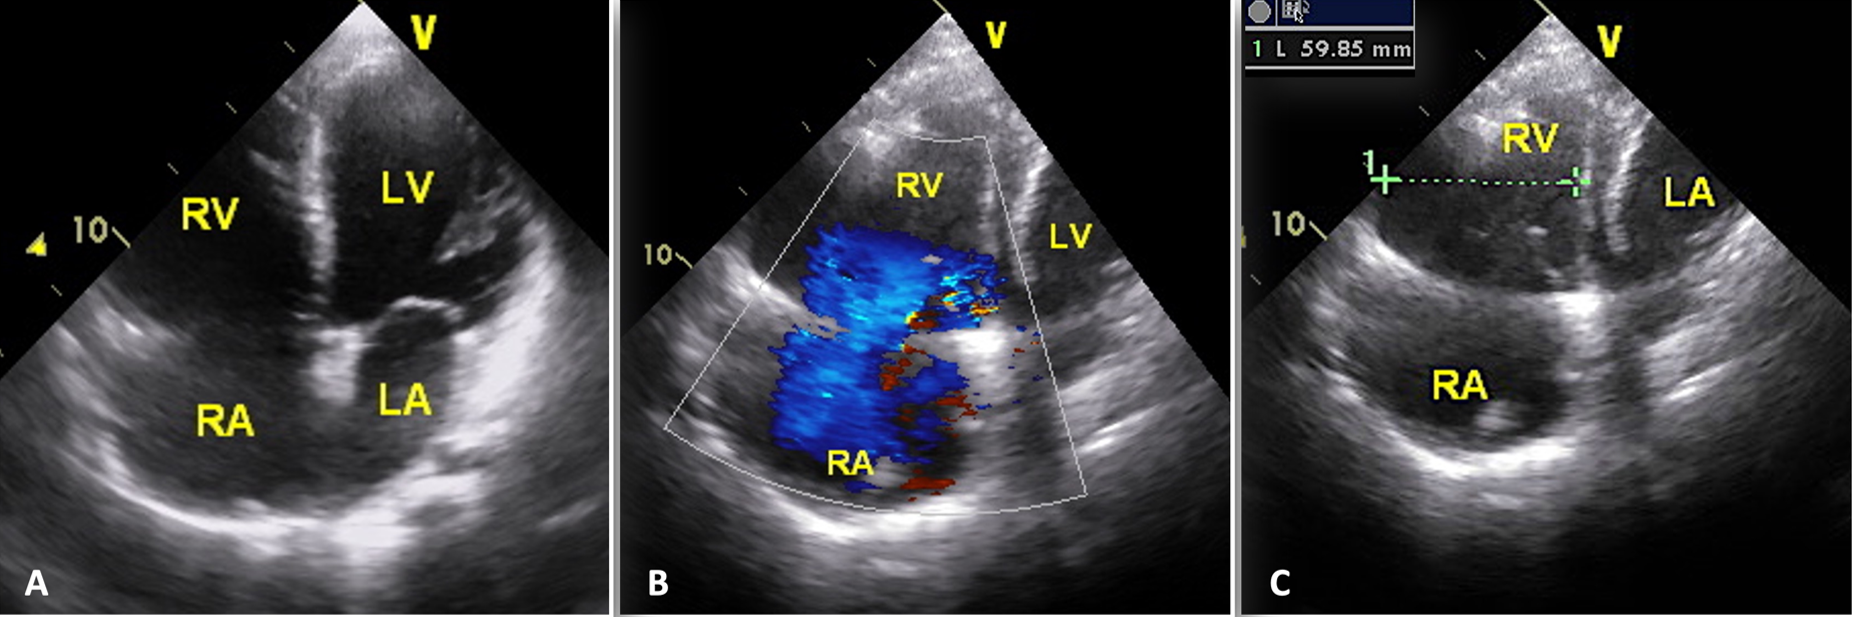

A 13-year-old male patient was admitted with complaints of chest pain and shortness of breath with exertion for 2 months. He was referred to our institution with a prediagnosis of ARVC and heart failure. Physical examination findings were as follows: Mild tachycardia (120-130 bpm), tachypnea (38/min), a 2-3/6 pansystolic murmur best heard at the left lower sternal border, jugular venous distension, a liver palpable 3 cm below the costal margin and mild ascites. Electrocardiogram showed; sinus tachycardia (110 bpm), a widened QRS (120 msec) and the corrected QT interval (QTc) of 480 msec (because of widened QRS) (Fig. 1). Echocardiography revealed significantly reduced biventricular function (left ventricle M-mode ejection fraction: 15%), enlarged right heart chambers with a RV diameter of 53.8 mm (z score: + 4.08) in apical 4 chamber view and severe tricuspid regurgitation (Fig. 2). Cardiac MRI showed marked dilation of the right ventricle (RV) with an indexed volume of 149 mL/m2 and hypokinesia in the free and inferior walls, as well as segmental wall thinning and focal late gadolinium enhancement (Fig. 3). The ejection fraction was 10% and 15% for the right and left ventricles, respectively. Heart failure treatment was administered immediately and a 24-hour-rhythm Holter was planned. On the second day of hospitalization, the patient had a sudden cardiac arrest and during cardiopulmonary resuscitation, it was recognized that the patient had VT exhibiting LBBB morphology with an intermittent transition to ventricular fibrillation (VF). Multiple antiarrhythmics including lidocaine, amiodarone, and magnesium were administered and the arrhythmia was converted to sinus rhythm after 5 cardioversions and 2 defibrillations. The patient was transferred to the pediatric intensive care unit (PICU). During follow-up in the PICU, the patient had episodes of LBBB morphology VT with intermittent transition to VF despite amiodarone and lidocaine infusion and was re-arrested. During cardiopulmonary resuscitation (CPR), venoarterial extracorporeal membrane oxygenation (ECMO) was initiated in 35 minutes. As drug-resistant VT storm continued during ECMO support, a single staged endocardial and epicardial approach for ablation was planned along with the assistance of cardiothoracic surgery. Even though the epicardial scar was much larger than the endocardial scar, a clinical VT isthmus was present at the endocardial site where ablation terminated the VT quickly (Fig. 4). An implantable cardiac defibrillator was implanted for secondary prevention, amiodarone was administered, and the patient was decannulated on the 4th day. The patient was discharged without any sequelae meanwhile autosomal dominant mutation that is linked to ARVC was detected in DSC2 gene at 18q12.1. Three months later the patient was rehospitalized for decompensated heart failure (NYHA class III-IV). Following this, his clinical status deteriorated due to multidrug refractory and inotrope-dependent heart failure. His kidney functions worsened, he became symptomatic even at rest, and developed massive hepatomegaly and ascites which required multiple paracentesis but never experienced sustained and hemodynamically significant arrhythmia. He could not be discharged and was on inotropes for 12 months till he underwent a successful heart transplantation. Pathological analysis of the explanted heart revealed: diffuse degenerative changes characterized by nuclear hyperchromasia, centralization and pleomorphism, areas of mucinous degeneration and oedema under the endocardium, mucinous degeneration in the valves, fibrosis between muscle fibers, congestion and fibrin accumulation sites in the pericardium and also a quite thin right ventricle wall. The patient has been followed up for 9 months and shown no symptoms post-transplantation.

B: severe tricuspid regurgitation; C: apical 4-chamber view with RV dimension.